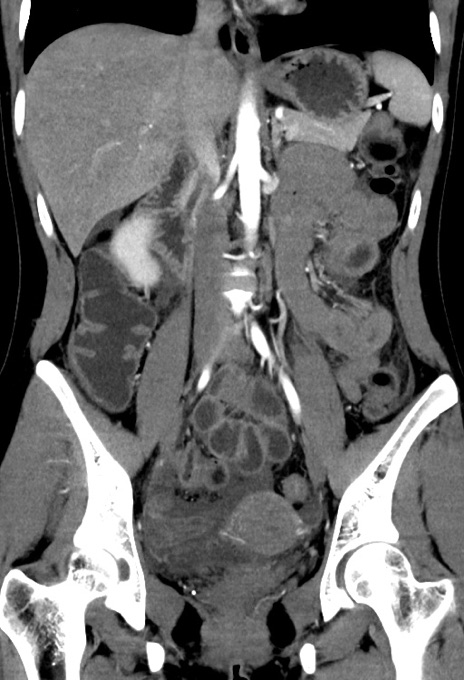

症例17(冠状断像)

【症例】20歳代女性

【主訴】嘔吐、下腹部痛

【現病歴】昨日夕食後に嘔吐し下腹部痛が出現。本日になっても嘔吐持続し改善しないため来院。

【身体所見】意識清明、BT 37.2℃、BP 108/67mmHg、腹部:平坦、やや硬、下腹部正中から右にかけて圧痛あり、反跳痛軽度あり、tapping pain(+)。

【データ】WBC 13600、CRP 14.94